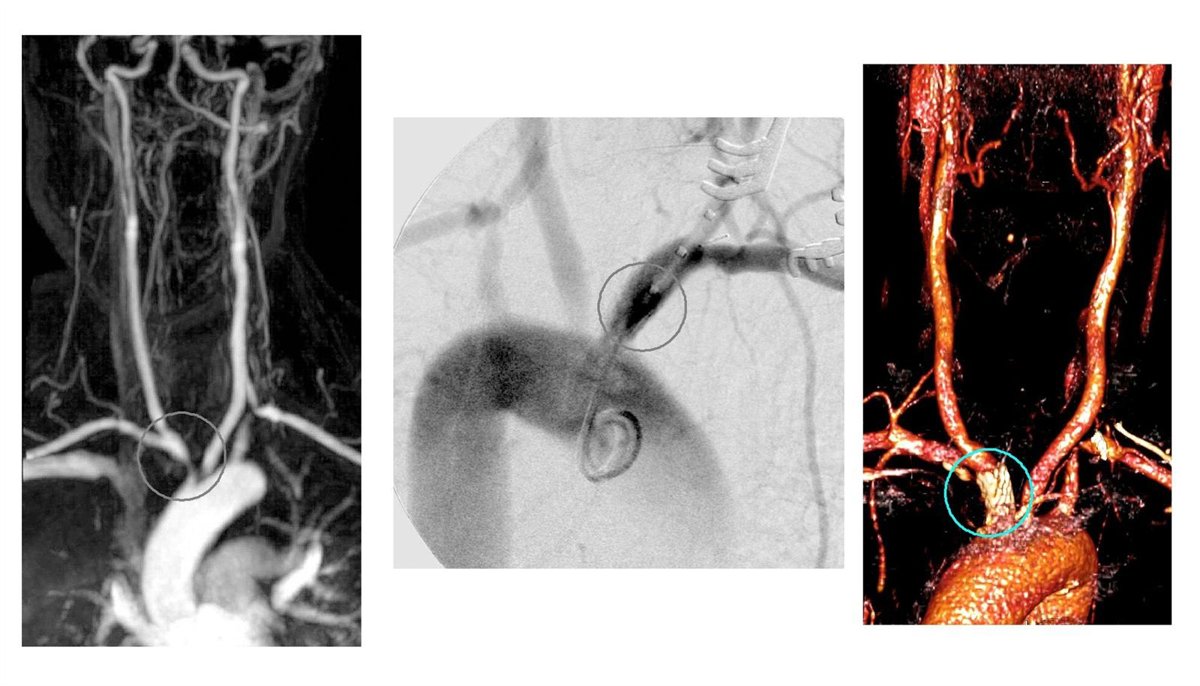

Imágenes De La Intervención En El Hospital Peset

El Servicio de Angiología y Cirugía Vascular del Hospital Universitario Doctor Peset ha realizado por primera vez en el mundo una intervención quirúrgica novedosa para solucionar el estrechamiento crítico (estenosis) que una mujer de 42 años sufría en el tronco braquiocefálico (una de las ramificaciones mayores de la aorta) y que le ocasionaba pérdidas de visión de corta duración en el ojo derecho y dolor al esfuerzo en los brazos, según ha informado la Generalitat en un comunicado.

"En algunos casos graves, además del tratamiento con fármacos, es necesaria la cirugía para evitar las complicaciones que puede causar el estrechamiento de las arterias. Éste era el caso de nuestra paciente, puesto que, tras realizarle varios estudios, se comprobó que tenía una estenosis crítica de tronco braquiocefálico y que presentaba alteraciones en la arteria carótida derecha, vertebral y subclavia (arteria del cuello) que producían diversos síntomas de consideración", según ha explicado el doctor Eduardo Ortiz, jefe del Servicio de Angiología y Cirugía Vascular del Hospital Universitario Doctor Peset.

Así, la paciente fue sometida a una angioplastia, un procedimiento que consiste en introducir un balón para dilatar una arteria ocluida y restaurar el flujo sanguíneo, y se lo colocó un stent (especie de malla cilíndrica) en el tronco braquiocéfalico para evitar un nuevo estrechamiento.

El resultado de la intervención fue la desaparición de los síntomas que presentaba la paciente y la recuperación de los pulsos carotídeo (en el cuello) y radial (en la muñeca) derechos. Es decir, la sangre bombeada por el corazón volvió a circular con normalidad por estas arterias.

Lo novedoso del caso es que en lugar de realizar el cateterismo a través de la arteria femoral, los cirujanos vasculares del Hospital Universitario Doctor Peset utilizaron un abordaje carotídeo, en este caso, por la arteria carótida derecha.

"Este abordaje únicamente precisa de una pequeña incisión en el cuello, nos permite un acceso directo a la zona del estrechamiento y posibilita la protección cerebral mediante el cierre momentáneo de la circulación cerebral durante la angioplastia. Así evitamos una posible isquemia que se produciría si con el catéter se soltara un trombo y fuese a parar al cerebro, obstruyendo la llegada de sangre, y, por lo tanto, de oxígeno a una determinada área cerebral", ha afirmado el doctor Ortiz.

En la literatura científica mundial hay menos de 10 casos descritos de tratamiento endovascular de la arteritis de Takayasu y en todos ellos se realizó un abordaje a través de la arteria femoral. La intervención exitosa realizada en el Hospital Universitario Doctor Peset es la primera en el mundo que utiliza el abordaje carotídeo.